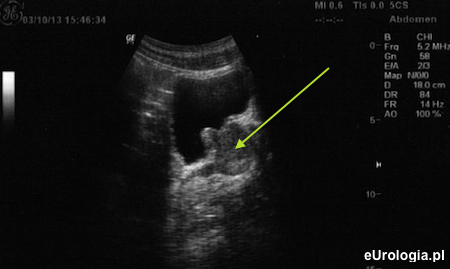

Fot. Przekrój strzałkowy w badaniu USG przez powłoki brzuszne. Wpuklający się do pęcherza moczowego gruczoł krokowy z przerośniętym trzecim płatem.